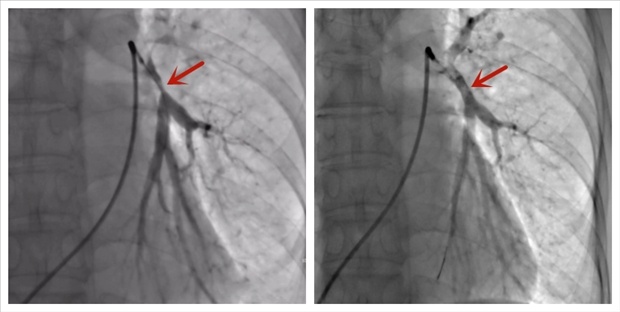

由于增生的纤维组织比较坚硬,单纯使用球囊很难将狭窄的血管完全撑开。医生们决定,在史先生狭窄的肺动脉内置入一枚金属支架,撑起“供氧生命线”。

术前肺动脉明显狭窄(左),术后肺动脉恢复通畅(右)。